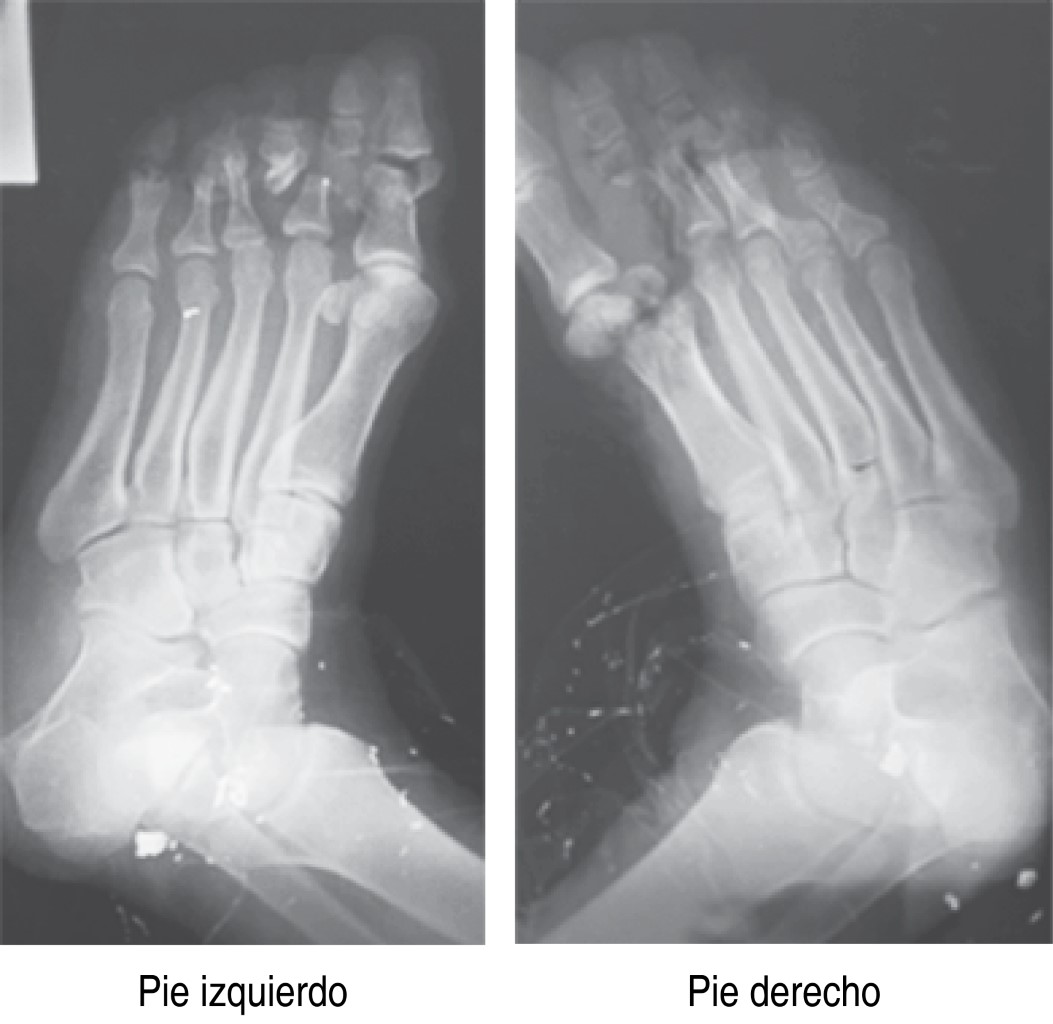

Actualmente el paciente se muestra con marcha plantígrada (Figuras 5 y 6), sin deformidad en equino, con apoyo completo, sin dolor a la flexión plantar, dorsiflexión de 0o, heridas quirúrgicas en completo estado de cicatrización, cuenta con ortesis, con adecuada rehabilitación física, apto para realizar actividades físicas de la vida diaria.

Figura 5

Figura 6